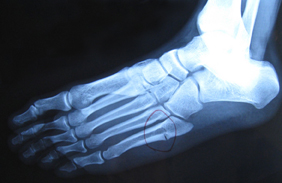

这种先天性畸形是非常复杂的,外观与跖骨内翻很像,它是合并后足掌屈、中足外展及前足内旋的复杂性先天异常。如果合并有跟腱挛缩,将会造成婴幼儿在练习站立或走路时的不适。如果没有及时且适当的治疗,将会导致青少年时期走路时的疼痛及后遗症。在X光的照射下,会发现小宝宝的前足、中足、后足呈现不规则的Z字型异常。